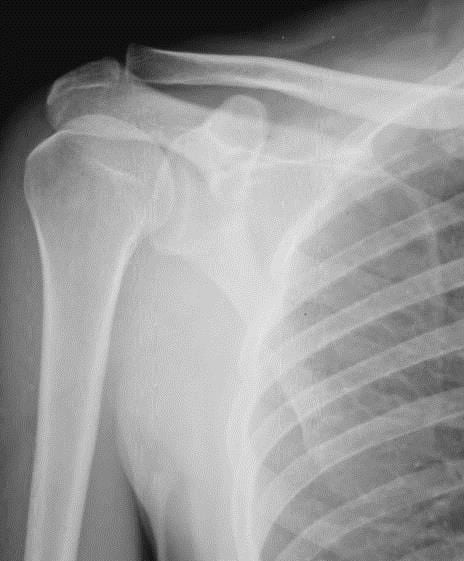

Если причиной заболевания стала травма, то проводится рентгенологическое исследование, чтобы исключить перелом надмыщелка. МРТ или КТ назначается при трудностях с дифференциацией эпикондилита и синдрома кубитального канала или синдрома круглого пронатора. Биохимические анализы показаны при подозрении на инфекционный, ревматоидный, реактивный артрит, подагру.